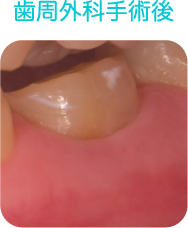

歯周外科治療

歯周基本治療で改善することができなかった深い歯周ポケットの除去

歯周組織の再生

口腔環境の改善